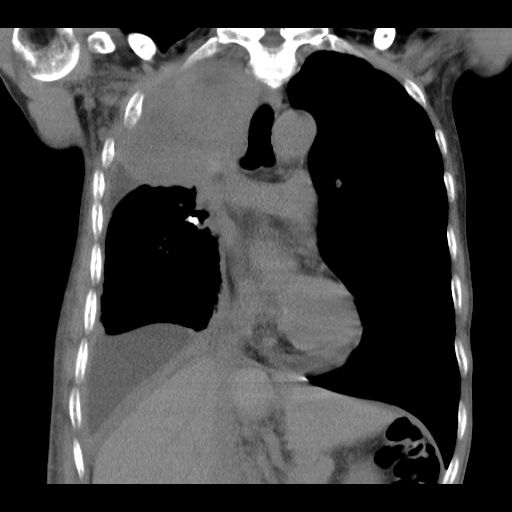

2020年5月12日,何叔來到復大就診,檢查結(jié)果:入院查CT示右肺中央型肺癌并右肺上葉及中葉阻塞性肺不張表現(xiàn),肺腺癌T3bN2M1 Ⅳ期,伴胸膜、縱膈、右肺門等多發(fā)淋巴結(jié)轉(zhuǎn)移,左側(cè)胸腔中大量積液,右側(cè)胸腔少量包裹性積液。針對何叔的病情,復大專家團隊立馬組織會診,先后給予何叔靜滴安維汀和兩次動脈DSA+灌注化療聯(lián)合PD-1治療,何叔的呼吸癥狀得到改善,腫瘤也從8.6公分縮小到4公分。

治療后